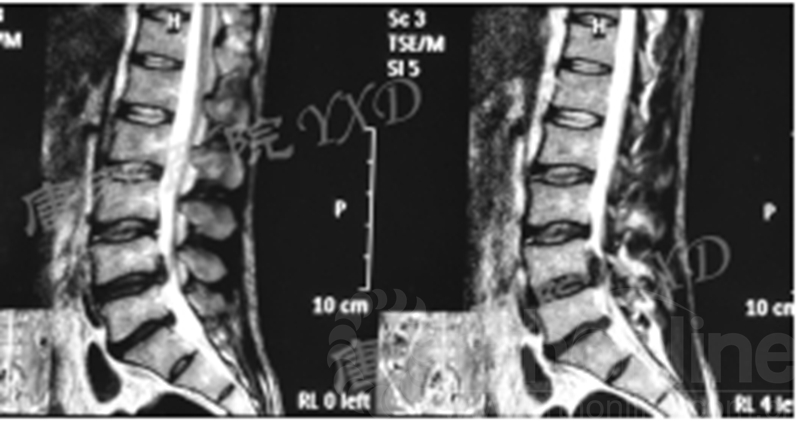

影像学检查:

诊断:腰椎间盘突出症术后复发

手术方案:显微镜辅助MI-TLIF腰椎翻修术

术中视频:http://api.orthonline.com.cn/attach/Case2.mp4(术中发现因前三次侧路及后路内镜手术的操作,术区大量瘢痕组织增生、与神经粘连严重;此外,摘除头侧游离髓核时连接有软骨终板脱落;在显微镜操作下,安全地将神经进行充分松解,压迫神经的游离髓核及软骨终板彻底清除。无手术并发症)